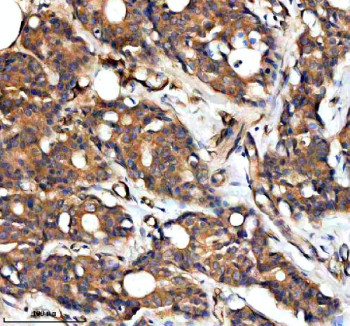

Adding 0.2 ml of distilled water will yield a concentration of 500 ug/ml. The RAPH1 antibody targets Ras-associated and pleckstrin homology domains-containing protein 1, a membrane-associated adaptor encoded by the RAPH1 gene. Also known as lamellipodin, this protein coordinates actin cytoskeleton remodeling, cell migration, and adhesion through interactions with Ena/VASP and small GTPases. Ras-associated and pleckstrin homology domains-containing protein 1 acts as a link between membrane signaling and actin polymerization, facilitating lamellipodia formation at the leading edge of motile cells. The RAPH1 antibody enables specific detection of this regulatory molecule in studies of motility, morphogenesis, and cell polarity.Ras-associated and pleckstrin homology domains-containing protein 1 contains Ras-association and pleckstrin homology domains that mediate binding to activated Ras and phosphoinositides, respectively. These domains anchor RAPH1 to the plasma membrane where it recruits actin regulators such as Ena/VASP proteins to promote filament elongation. The RAPH1 antibody supports localization studies revealing how this scaffold integrates receptor-mediated signaling with actin dynamics. Its enrichment at lamellipodia and adhesion sites underscores its central role in coordinating directional migration.RAPH1 interacts with the small GTPase Rap1 to influence integrin activation and cell adhesion. By bridging signaling pathways that control cytoskeletal organization, it contributes to epithelial integrity, immune cell motility, and neuronal pathfinding. The RAPH1 antibody allows visualization of these processes, providing insight into mechanisms governing cell migration during wound healing and development. RAPH1 dysfunction can impair motility or lead to aberrant invasion in tumor cells.Lamellipodin has also been implicated in cancer progression and metastasis. Its overexpression enhances actin polymerization and invasive potential in various cancers including breast and colorectal carcinoma. The RAPH1 antibody supports analysis of these oncogenic roles by enabling quantification of protein levels in tumor tissues. Additionally, RAPH1 participates in mechanotransduction pathways by translating substrate stiffness into cytoskeletal rearrangement, linking extracellular cues to motility responses.The RAPH1 antibody performs effectively in western blotting, immunofluorescence, and immunohistochemistry, yielding distinct membrane and cytoplasmic staining consistent with lamellipodial localization. NSJ Bioreagents provides this antibody as a validated, high-specificity reagent suitable for cell biology and oncology research. By enabling detailed study of Ras-associated and pleckstrin homology domains-containing protein 1, the RAPH1 antibody advances understanding of cytoskeletal signaling, adhesion regulation, and directional migration in physiological and pathological contexts.

| Application: | WB, IHC, ELISA |